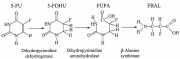

| 19:30, 29 באוקטובר 2017 | DPYD4.jpg (קובץ) |  |

72 קילו־בייטים | Motyk | 1 | |

| 19:18, 29 באוקטובר 2017 | DPYD3.gif (קובץ) |  |

3 קילו־בייטים | Motyk | 1 | |

| 19:08, 29 באוקטובר 2017 | DPYD2.png (קובץ) |  |

149 קילו־בייטים | Motyk | 1 | |

| 19:02, 29 באוקטובר 2017 | DPYD1.png (קובץ) |  |

533 קילו־בייטים | Motyk | 1 | |